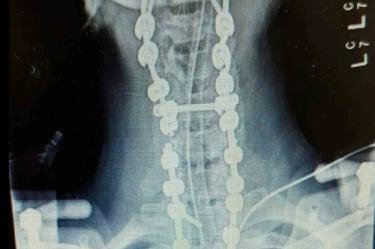

Megan fue operada de emergencia y así los médicos lograron fusionar el cráneo a la columna vertebral y logró sobrevivir a la terrible decapitación, que, de acuerdo con estadísticas, tiene una tasa de mortalidad del 90% debido a la probabilidad de que las señales nerviosas entre el cerebro y el cuerpo se dañen, lo que provoca parálisis en órganos vitales como los pulmones y el corazón.

Hasta el momento, la mujer lleva un total de 37 cirugías desde su accidente, dejando su cuerpo fusionado desde el cráneo hasta la pelvis y su cabeza incapaz de moverse en ninguna dirección.